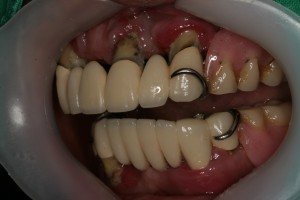

이 환자분은 위아래 틀니를 사용하시는 분인데 틀니를 거는 지대치인 앞니가 많이 흔들린다며

내원하셨습니다. 구강 내를 살펴보니 구강위생이 좋지 않아 치태,치석도 많고 잇몸이 많이 부어 있었습니다.